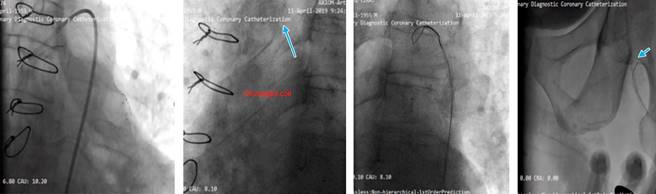

Our aim was to use the SVG as retrograde conduit for CTO PCI. During the procedure stenting was done but the stents balloon ruptured and made a huge dissection which caused a hematoma (Figure 4). As a bailout solution we decided to stent from the ostial LCx (Figure 5). To maintain a sufficient coronary perfusion, we decided to coil occlude due to Thrombolysis in Myocardial Infarction Score (TIMI) flow over 2 in this stenotic and thrombotic SVG so the competitive flow won’t affect the newly opened CTO’s long-term results. While coiling the donor SVG the coil dislodged. During the attempt to snare the dislodged coil with single loop snare, force by this device resulted in fracture in the dislodge coil and made two separated particles. One particle stayed in the descending aorta and the other went to the femoral artery. Both then were snared eventually (Figure 6).

Coil occlusion of SVGs is commonly employed to reduce competitive flow; however, in this case, coil dislodgement led to additional complications. The retrieval of coil fragments from both the descending aorta and femoral artery demonstrates the importance of having a bailout plan in such high-risk interventions.4

Moreover, the fracture of the coil during snaring highlights the need for careful handling of retrieval devices to avoid exacerbating complications.

Stenotic or occluded SVGs should be considered the primary retrograde route for CTO PCI when available, as they often lead to fewer complications and greater procedural success compared to other collateral routes. Coil retrieval, when necessary, is best managed with three-looped snares, which are superior to single-loop snares for preventing coil fracture and subsequent embolization. This case highlights the importance of careful procedural planning and the ability to handle unexpected complications during complex coronary interventions.